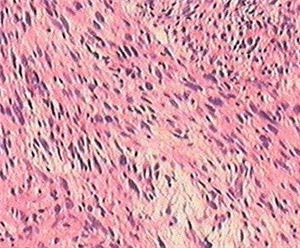

2.組織學形態纖維肉瘤根據其細胞形態及核分裂多少,鏡下可將其分為分化良好的纖維肉瘤和分化不良的纖維肉瘤兩類:

(1)分化良好的纖維肉瘤:鏡下見瘤細胞豐富,細胞形態類似纖維母細胞,呈梭形,形態整齊,均勻一致,異形性不明顯,核分裂不很多見。細胞核呈長梭形,深染,分布均勻,胞漿不多呈粉紅色。瘤細胞與膠原纖維一起排列呈編織狀。此型纖維肉瘤有浸潤性生長,局部切除後可復發,但無轉移傾向。

(2)分化不良的纖維肉瘤:鏡下見瘤細胞豐富。呈束狀交錯排列,有中等度到高度異形性,細胞不規則,呈圓形或卵圓形,梭形等。核分裂象多見。胞漿豐富,核大而深染。瘤細胞分化差,不產生膠原纖維,是一種惡性的未分化纖維肉瘤,極易轉移與復發。

1.組織病理學檢查 腫塊輪廓清楚,有假包膜。切面呈灰白色,有光澤或呈魚肉樣。鏡下見瘤細胞呈梭形,細胞核染色質較多,分布均勻;細胞質少,粉紅色。膠原纖維多與瘤細胞一起排列成人字形或羽毛狀縱橫交錯。嗜銀纖維較多,並圍繞每個細胞。2.免疫組化檢查 可見纖維肉瘤對Vimentin Ⅰ型膠原呈陽性反應。對平滑肌組織細胞標記或基底膜成分陰性者。